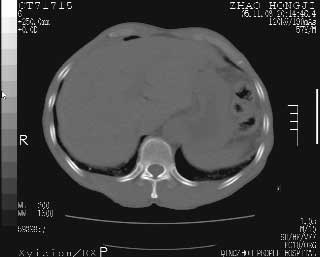

临床资料:男性,57岁,上腹部疼痛并5天,突然加重并延及全腹伴恶心5小时入院。胰淀粉酶化验在正常范围。检查:腹肌紧张,全腹压痛、反跳痛,尤以右上腹部为著。肠鸣音减低。血常规:wbc14.6x10/9, n:11.3x10/9 ,血压:135/90mmhg. 胸部透视:腹部肠腔轻度张气,未见其它异常改变。

肝右前缘少量积气,其他未见明显异常.考虑上消化道穿孔.

小网膜囊积气液,胃壁僵硬。考虑胃穿孔。

小膜网膜积液,肝缘气腹征,上消化道穿孔。

肝缘见少许气体,胰尾部见少许气体包饶(蓝色圈),12指肠上部或球部邻近胆囊周边也可见少许气体影(黄色圈),并忖托出胆囊壁,12指肠远段肠道内未见明显气体(白色箭)。

肝脏前缘见少量积气、胰尾部见少许气体包饶,肾前筋膜未见增厚,临床淀粉酶不高,意见:上消化道穿孔。

入院3小时后行剖腹探查术,见腹腔内大量脓性混浊液约1000ml,十二指肠球部溃疡穿孔,溃疡面约2.5x2cm,穿孔直径约0.6cm。胃内容物外益,周围组织炎性水肿明显。行十二指肠穿孔修补术。术后诊断:

1、十二指肠溃疡穿孔

2、弥漫性腹膜炎

对于少量的腹腔游离气体,ct检查较普通透视有绝对的优势,它不仅可以看到肝脏前上缘的气体,而且还能够看到小网膜区的游离气体。从而可以肯定诊断。各位分析战友的很好,感谢大家的参入!